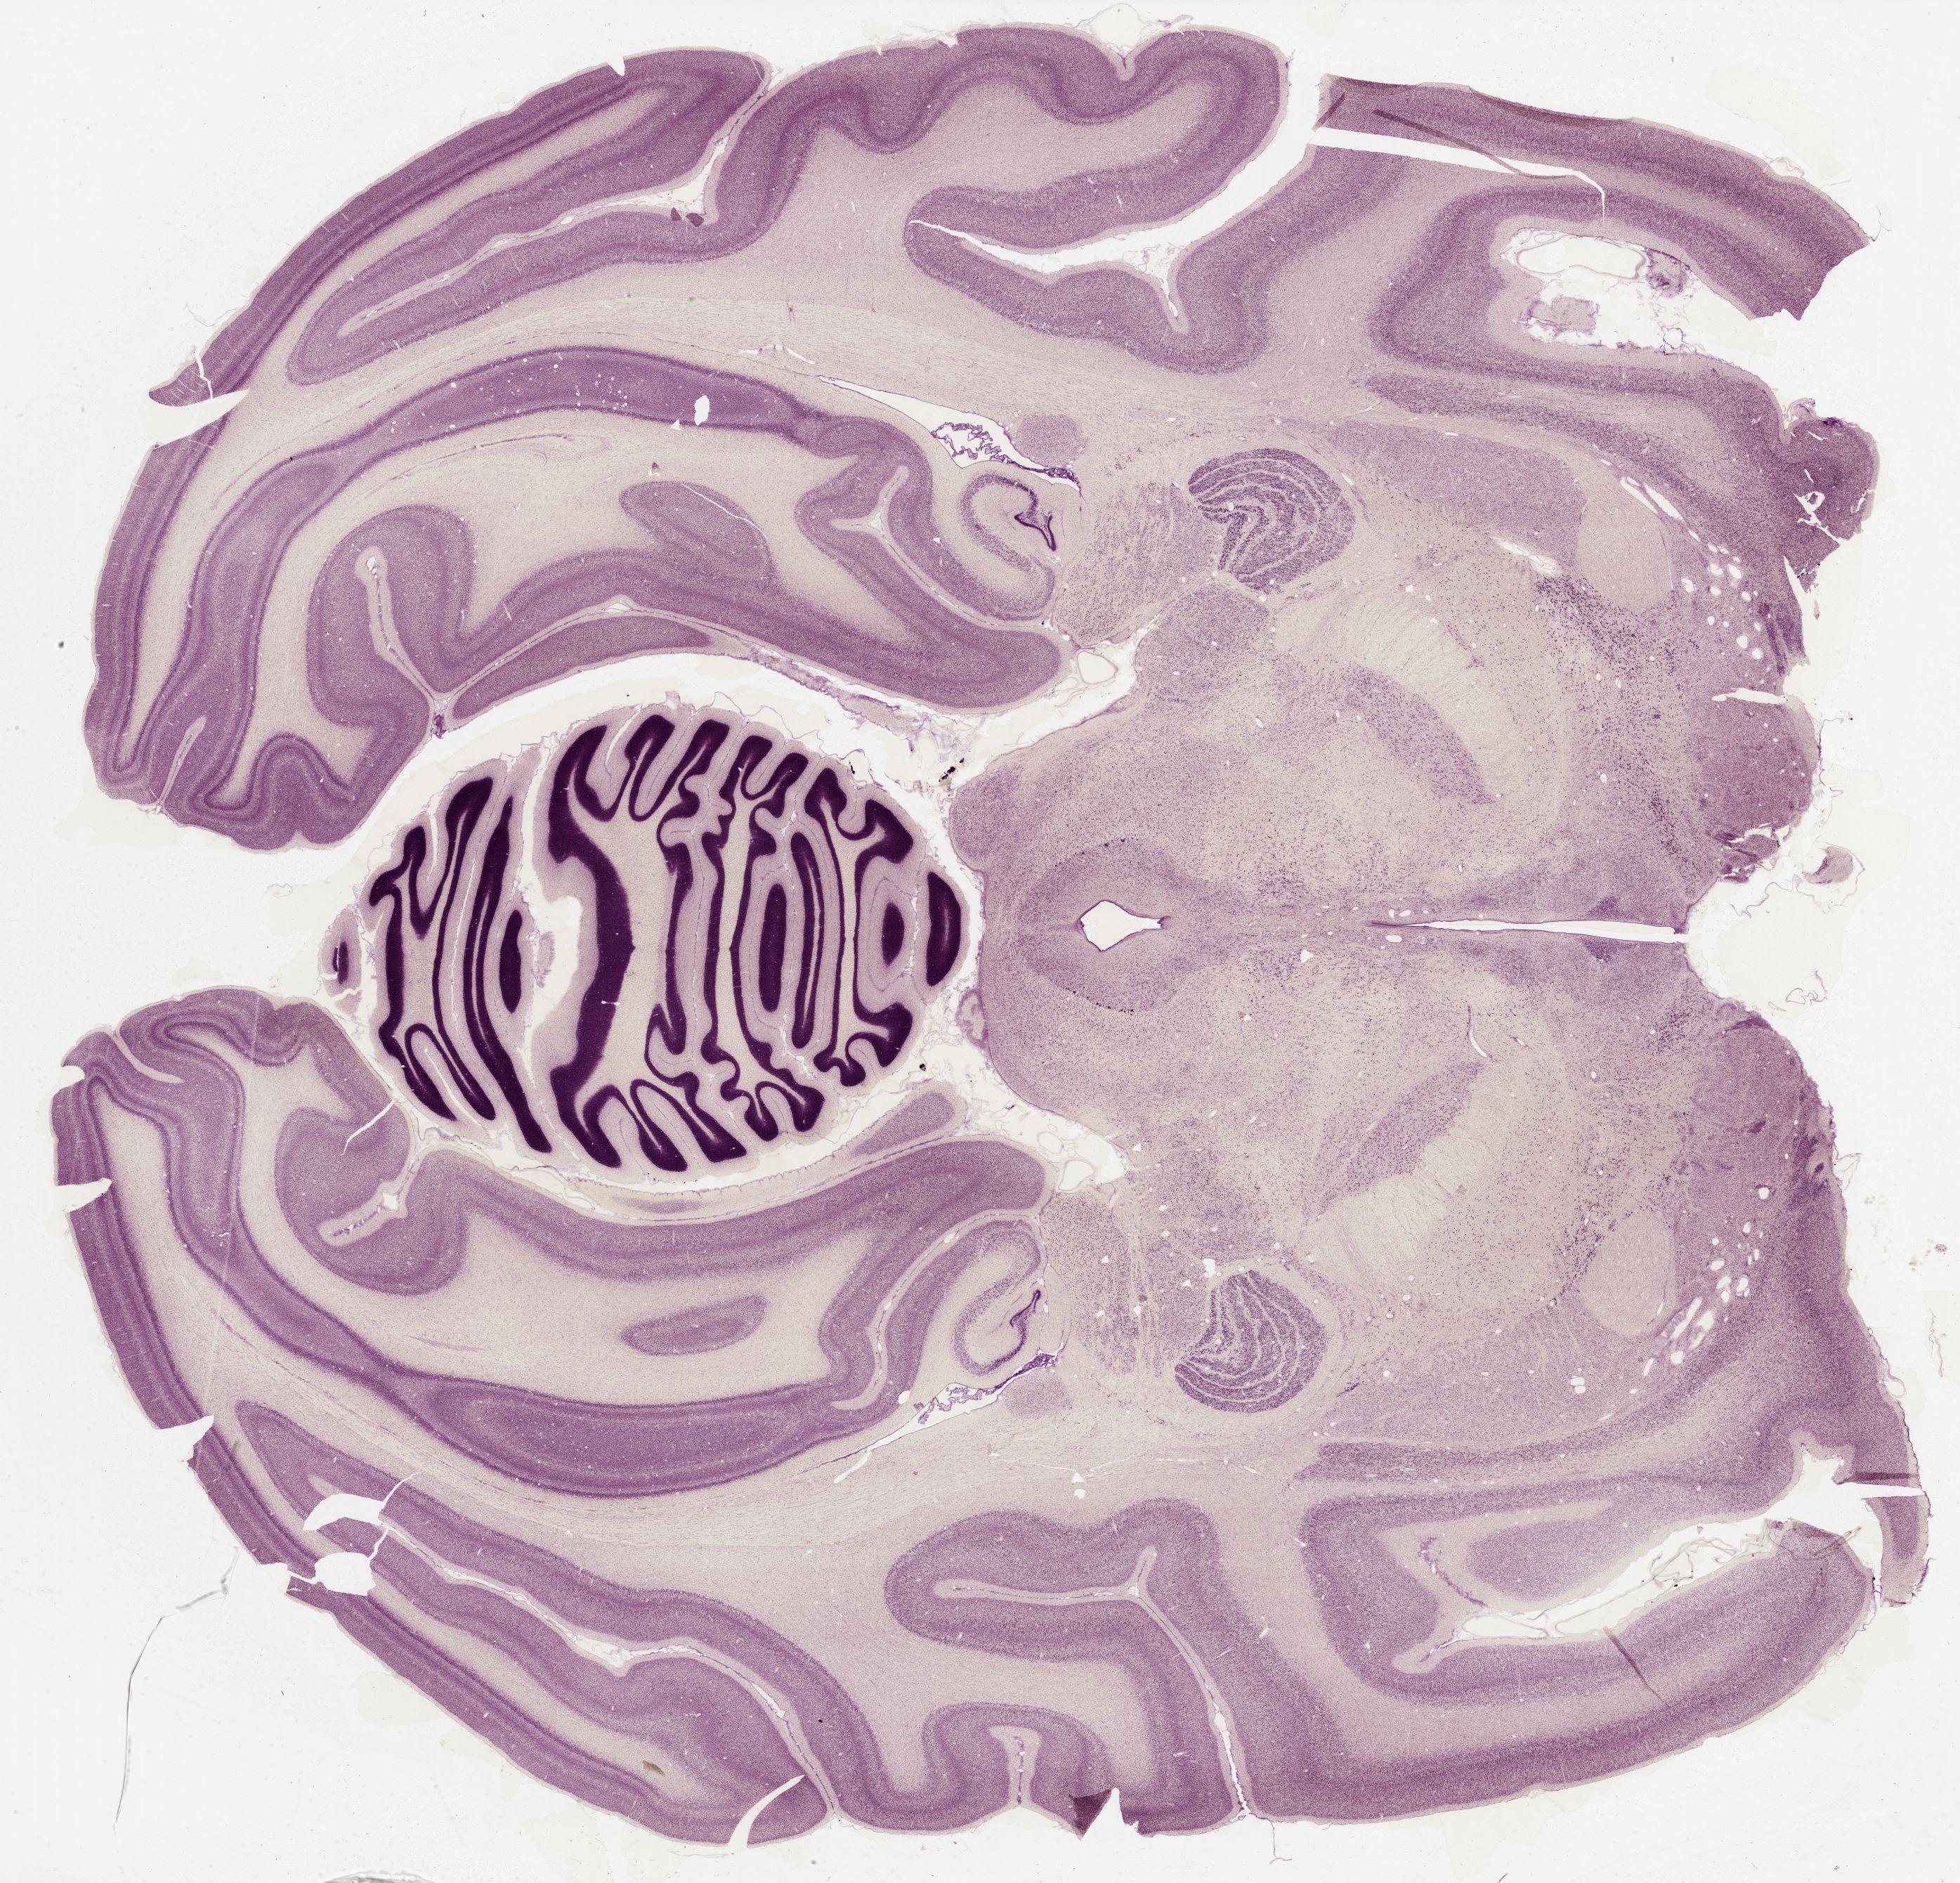

Datasets -> Macaca Mulatta -> Nissl, horizontal, histo, Whole-Brain, adult

[ Metadata ]   ·   Source: Edward G. Jones

Displaying Sections 81 thru 109 of 109 Sections for this Dataset